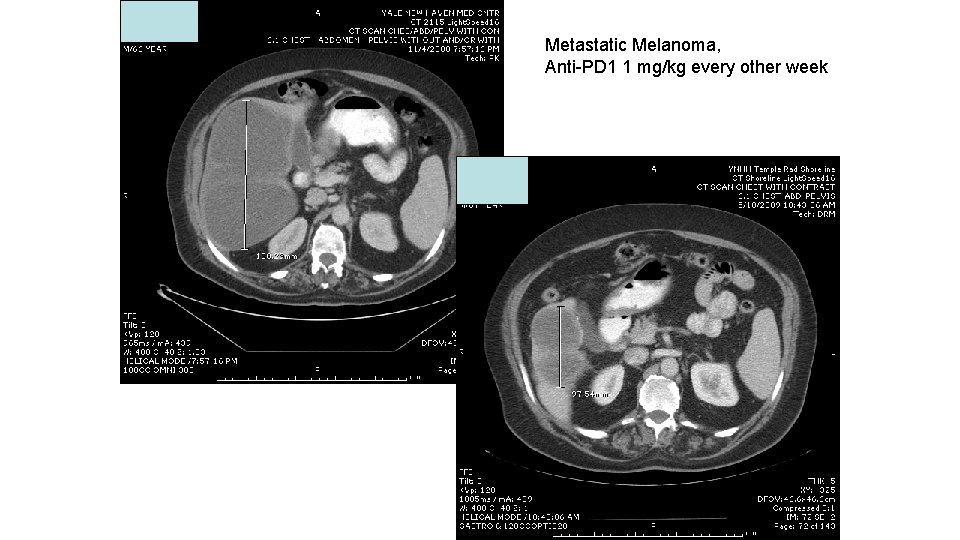

Metastatic Melanoma, Anti-PD 1 1 mg/kg every other week